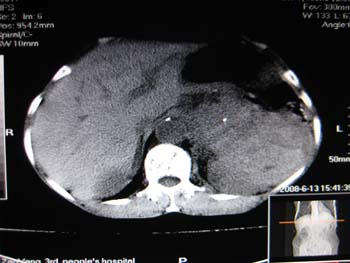

女,65岁,左上腹痛。

肝脏占位  脾脏及胰腺病变   请提供病史

肝脾胃左肾胰都显示不正常啊

病史不详,肝、脾、胰都有占位,谁是原发?

胰腺癌伴脾脏侵犯并肝内转移可能性大  建议增强扫描  否则没有确凿的依据

考虑姨尾癌,腹膜后转移\\肝转移

没有病史,没有强化,那就只有猜了,我看病灶很像肝、脾及腹腔多发脓肿,这只是我的意见,

图像欠清,病灶与胃脾胰肾上腺关系显示欠清,建议增强,肝脏考虑转移瘤.

多脏器占位,腹膜后淋巴结增大,淋巴瘤?建议增强扫描